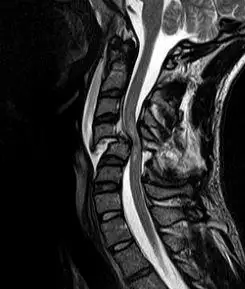

A radiographic evaluation using an X-ray, CT scan, or MRI can determine if there is damage to the spinal column and where it is located.[9] X-rays are commonly available[85] and can detect instability or misalignment of the spinal column, but do not give very detailed images and can miss injuries to the spinal cord or displacement of ligaments or disks that do not have accompanying spinal column damage.[9] Thus when X-ray findings are normal but SCI is still suspected due to pain or SCI symptoms, CT or MRI scans are used.[85] CT gives greater detail than X-rays, but exposes the patient to more radiation,[87] and it still does not give images of the spinal cord or ligaments; MRI shows body structures in the greatest detail.[9] Thus it is the standard for anyone who has neurological deficits found in SCI or is thought to have an unstable spinal column injury.[88]